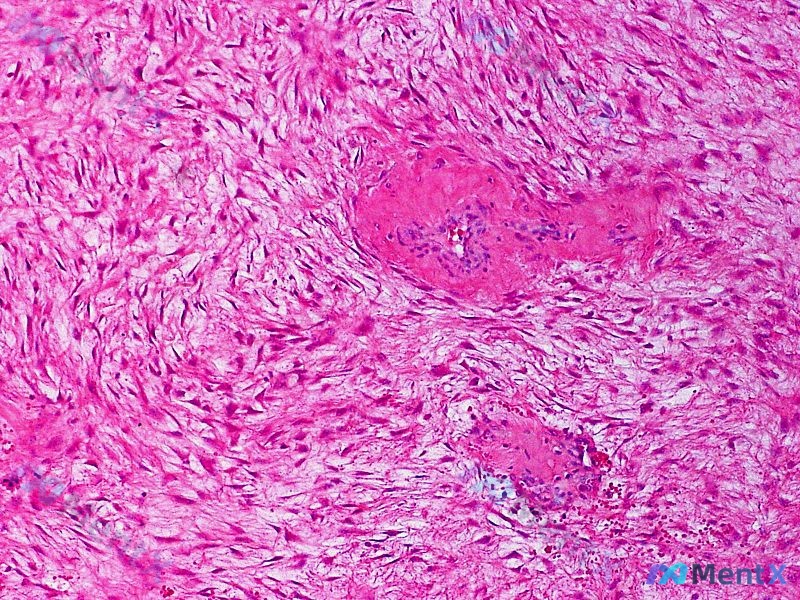

整理了一份病例讨论材料,几个关键点比较值得复盘。 患者信息:35 岁女性。 主诉:左肩后部有一个不断增大的无痛肿块。 体征:左上肢无无力或异常感觉。 家族史(重点):本人、母亲、兄弟、舅舅均有多发性结肠息肉、颌骨骨瘤和表皮样囊肿病史。 病理活检:显示真皮内大量增生的梭形细胞,呈旋涡状或束状排列,细胞...